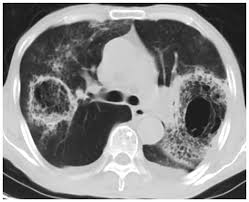

Ct Image Of Lung With Pulmonary Mucormycosis The Bilateral Lungs Show Download Scientific Diagram

Ct Image Of Lung With Pulmonary Mucormycosis The Bilateral Lungs Show Download Scientific Diagram from www.researchgate.net